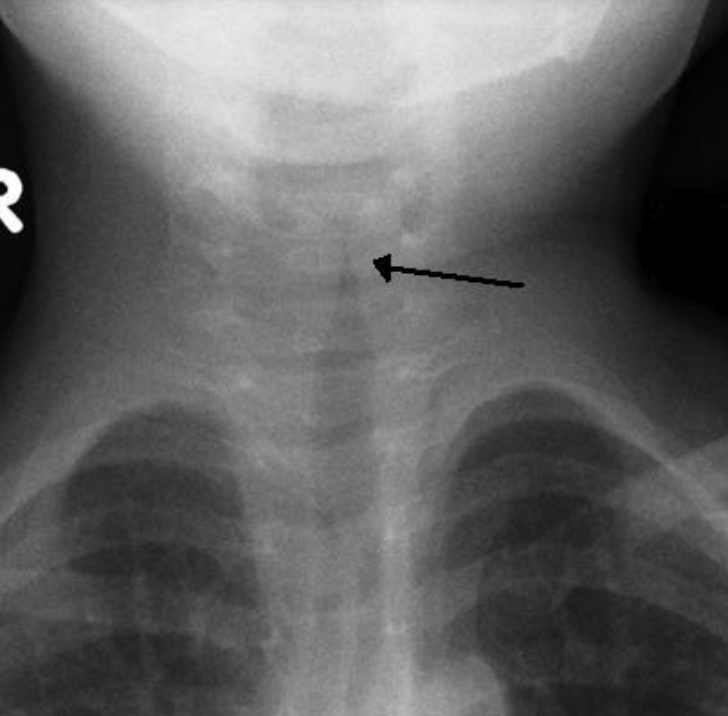

chest x-ray in croup

not required, but will demonstrate the steeple sign due to subglottic narrowing